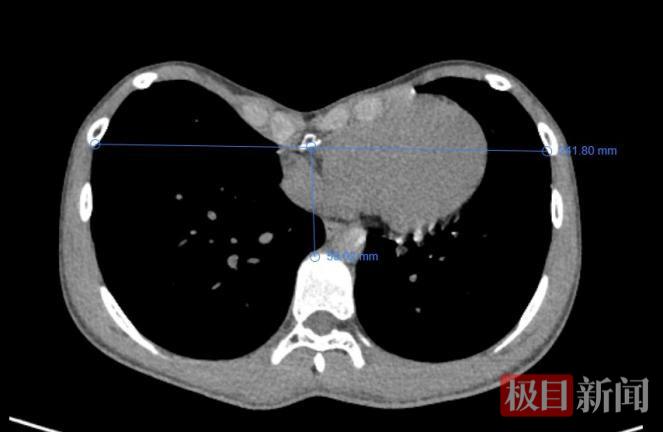

该科主任董永强接诊后,为小张进行了详细的评估,发现其漏斗胸指数达到4.08。临床上该指数大于3.25时,即提示胸骨凹陷较重,已对胸腔内器官形成明显压迫,属于手术干预的重要指征,小张已属于重度漏斗胸,董永强建议手术治疗。

董永强表示,漏斗胸是最常见的先天性胸壁畸形,其核心特征是胸骨中下部及相邻肋软骨向内凹陷,形成“漏斗状”畸形,严重时胸骨凹陷处可深达数厘米,不仅影响外观,更会压迫胸腔内的心脏、肺等重要脏器,引发胸闷、胸痛、运动耐力下降等症状,长期还可能导致心肺功能不可逆损伤。